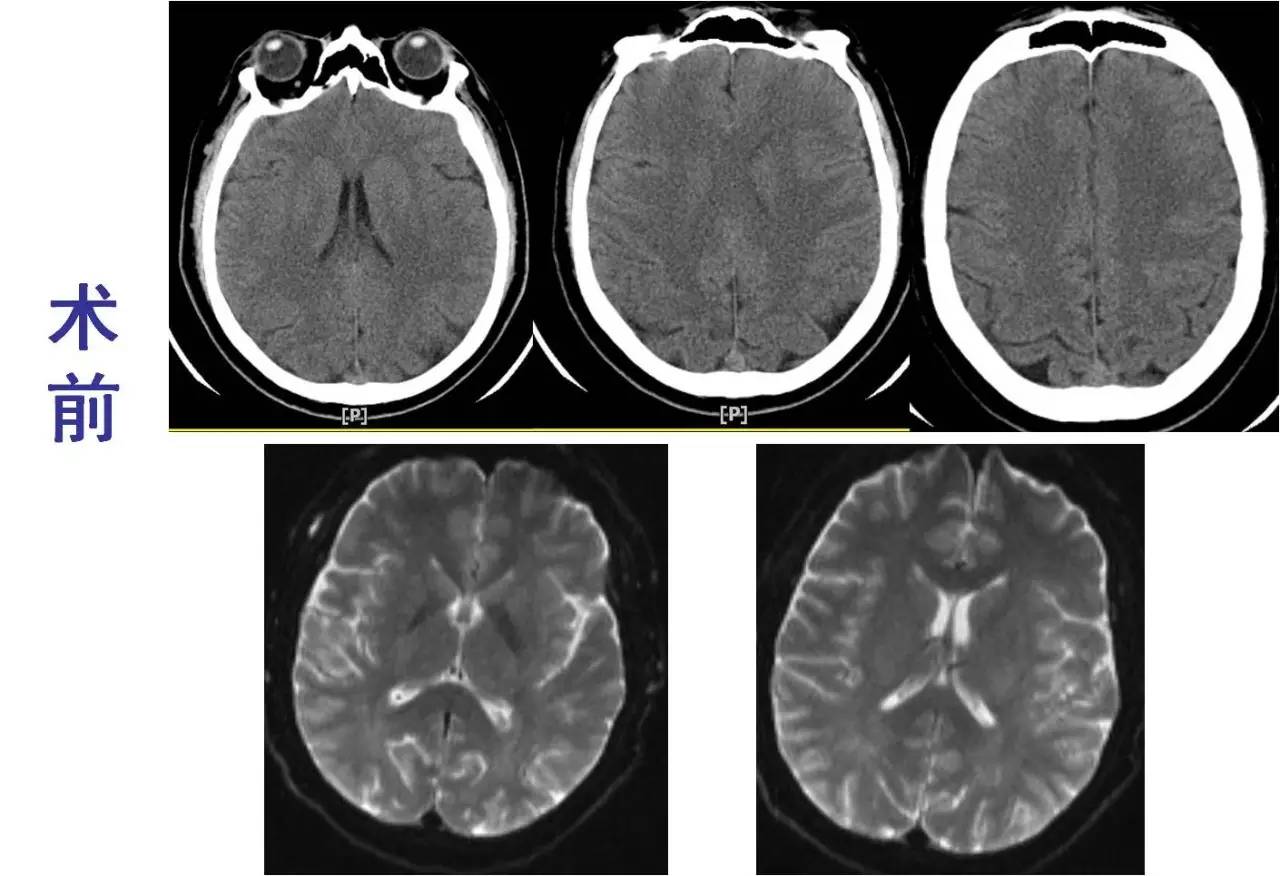

》CT:颅内未见出血;

》DSA:左侧大脑中动脉闭塞。

术前

术后

》意识清楚,言语流利,四肢活动自如;

》四肢肌力Ⅴ级;

》术后24小时NIHSS评分:0分;

》5天后主动脉换瓣术;

》90天mRS评分0分。